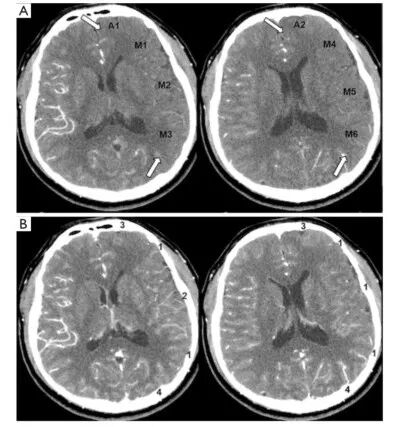

图3. 1例37岁男性患者,单侧烟雾病的CTP-Sis评分。A为动脉期,B为静脉期,箭头所指为低灌注区。